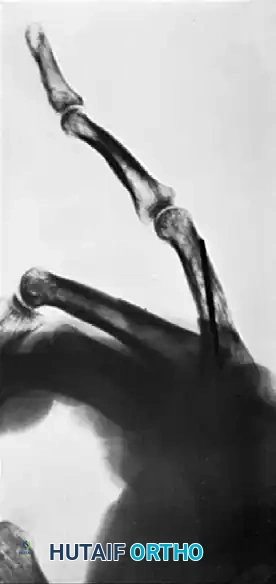

FIGURE 67-72: Malunited fracture of the fifth metacarpal neck treated by open reduction and fixation with one Kirschner wire inserted obliquely. This is rarely necessary because the normal motion of the fifth carpometacarpal joint permits tolerance of up to 40 degrees of angulation at the fracture site.